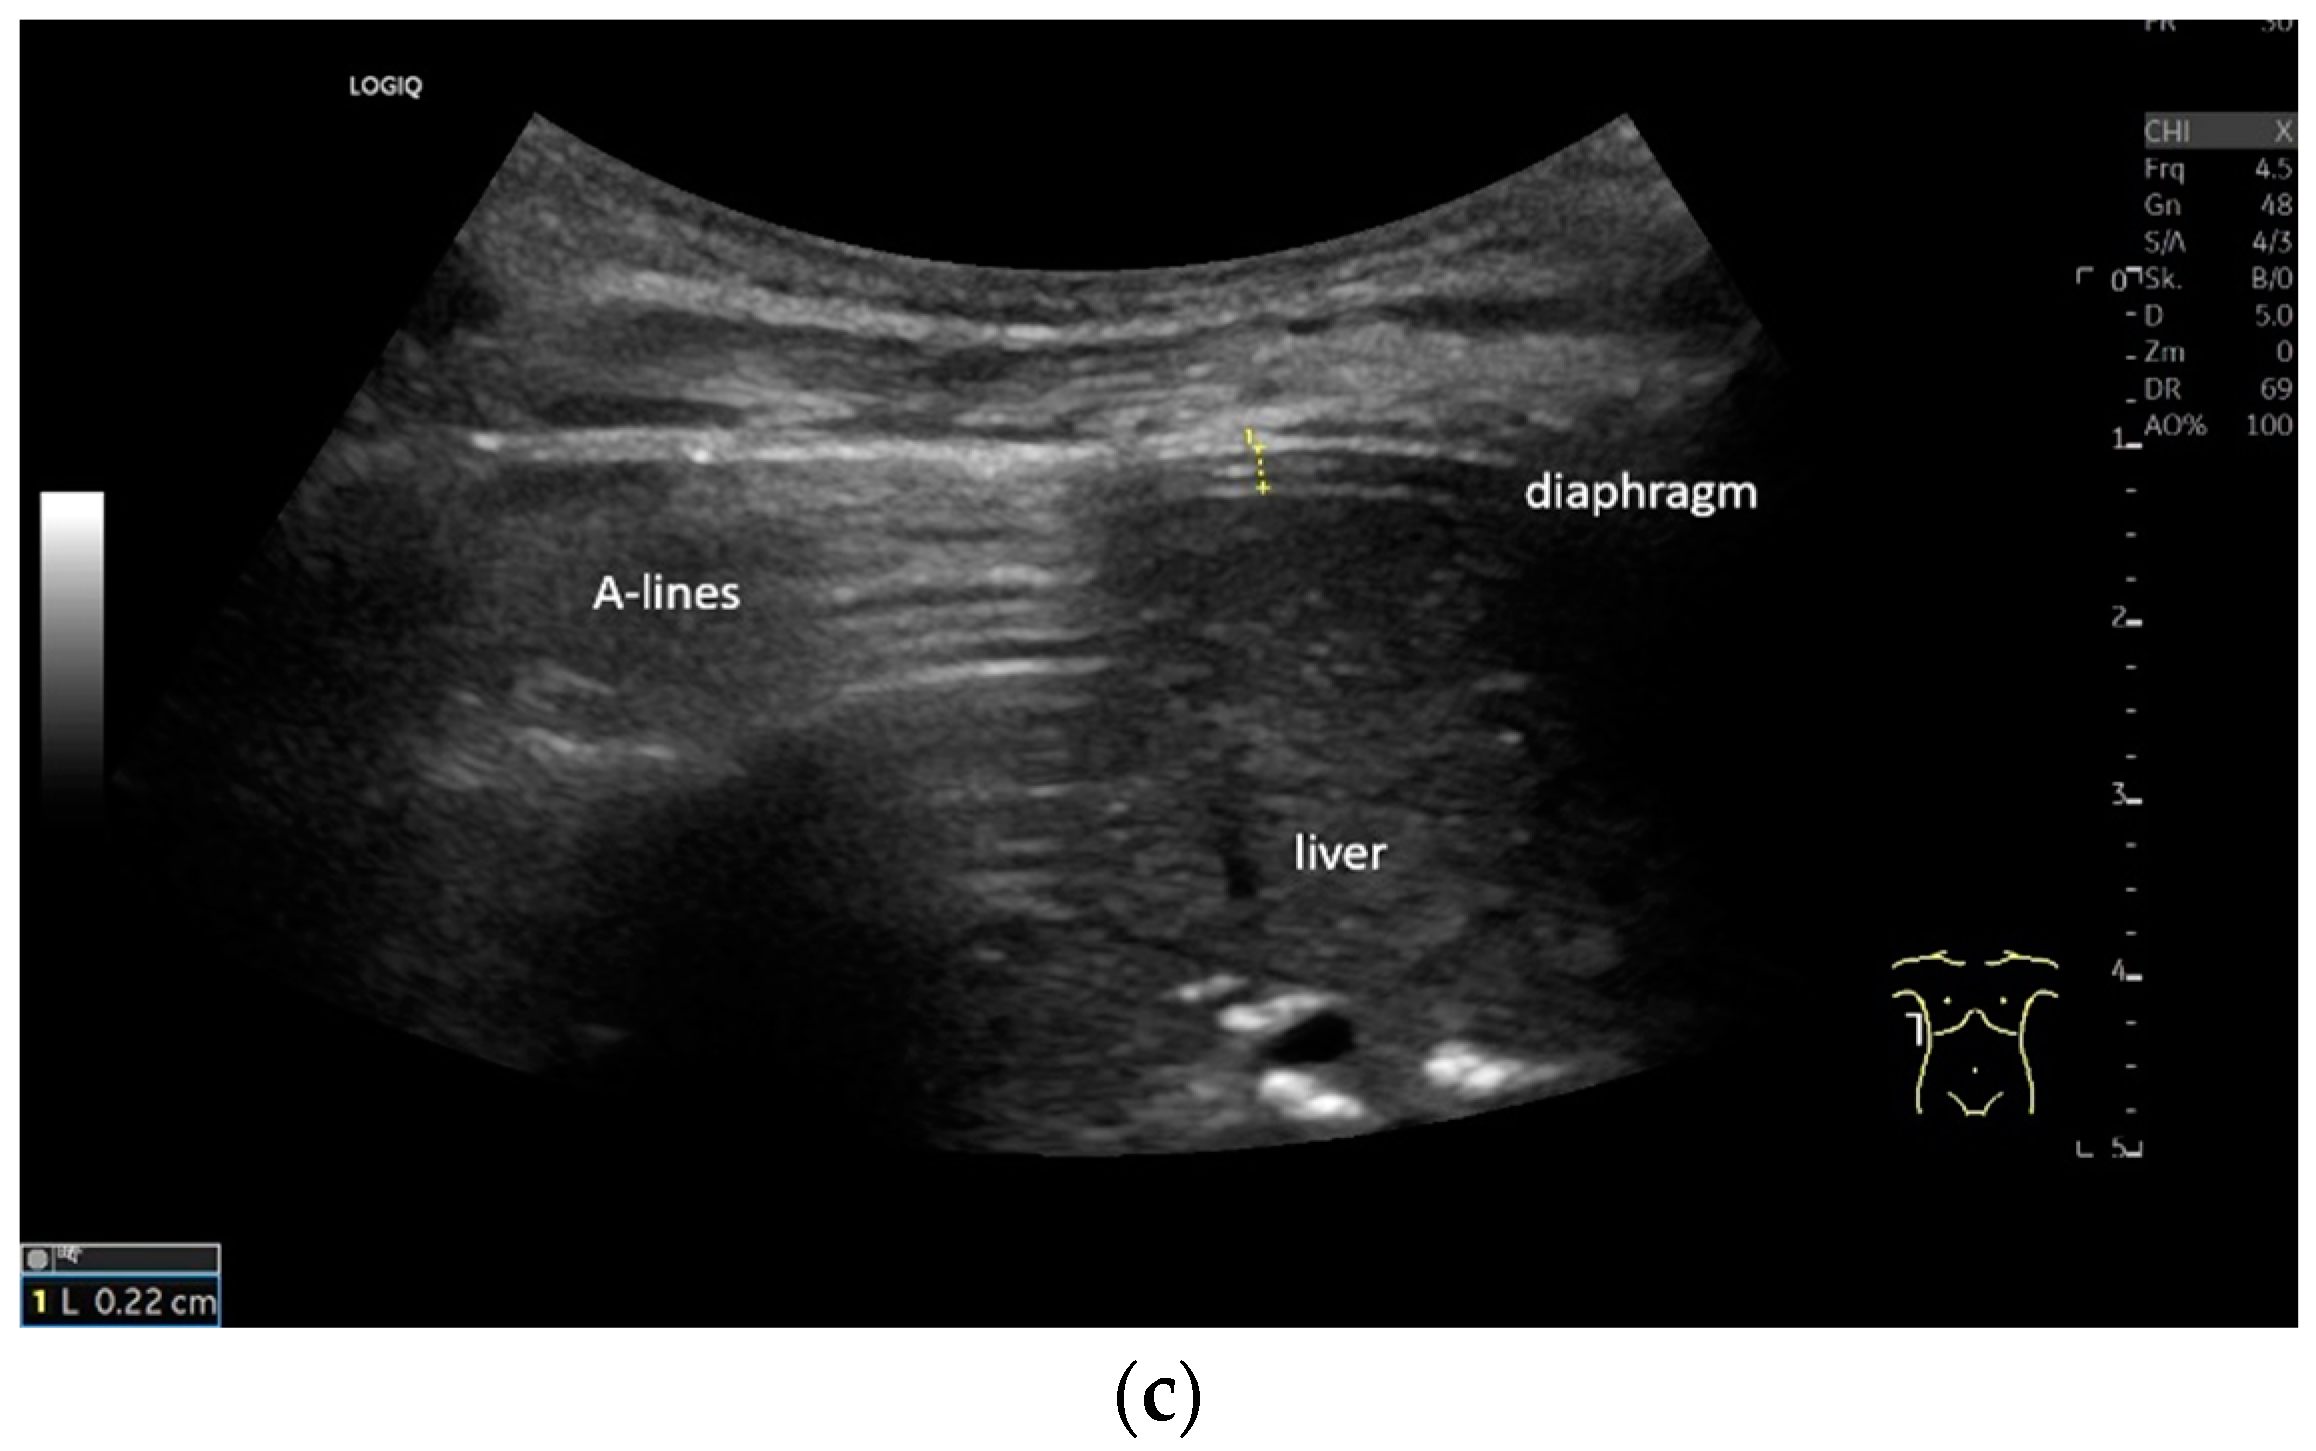

Lateral transducer position in the zone of apposition: The transducer is positioned longitudinally and laterally in the area of the mid-axillary line or slightly ventral to it between the anterior and mid-axillary lines, approximately in the 8th or 10th intercostal space. The diaphragmatic reflex is located on the inner side of the ribs below the pulmonary glide with pulmonary reverberations. This localization of origin of the diaphragm from the inner side of the rib cartilage is referred to as the zone of apposition (Figure 3). As this localization is only a few centimeters below the skin surface, high-resolution linear transducer use is highly recommended. In this position, the diameter of the diaphragm is measured during inspiration and expiration [2,3,4,5] (Figure 4). The thickness of the diaphragm varies, with caudal parts being thicker than cranial parts. The measurement of diaphragm thickness is highly variable depending on the intercostal space chosen, with thickness varying by up to 6 mm between the intercostal spaces [6]. It is therefore important to select the same position for comparable measurements and, if necessary, to mark the location for the transducer position [7]. Obesity limits assessment of the diaphragm [2].